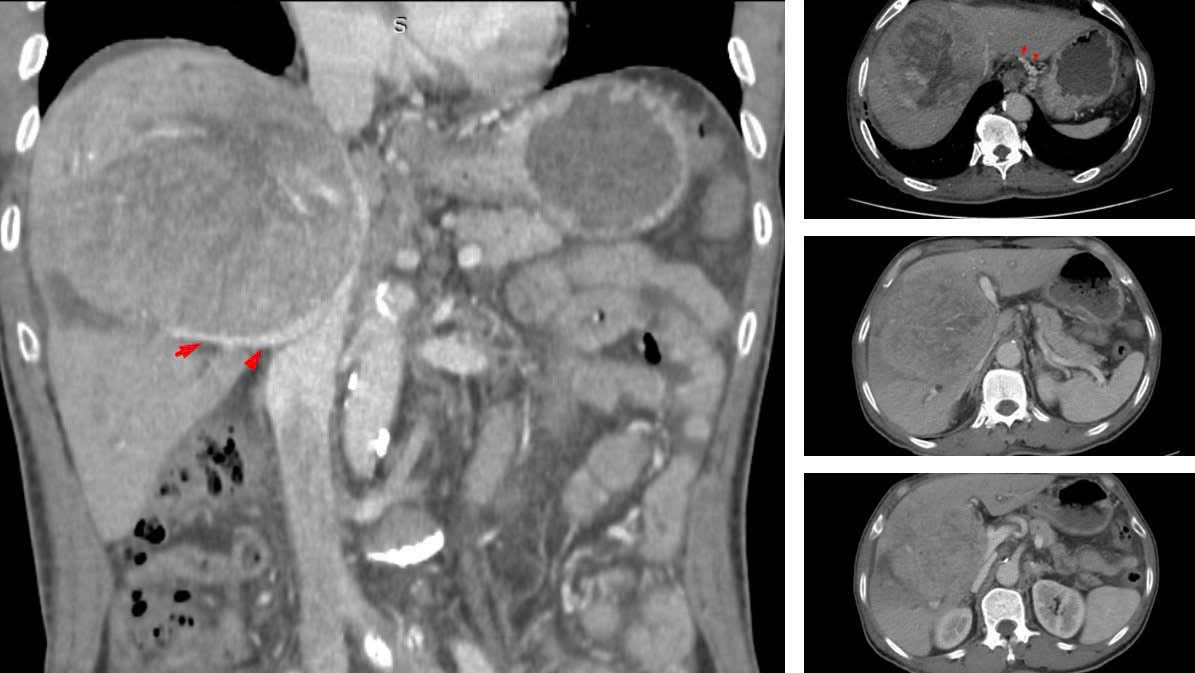

Hình ảnh khối u gan giai đoạn muộn. Ảnh: BVCC

BSCKII Nguyễn Trường Giang, Phó Giám đốc Trung tâm cho biết: “Khối u khổng lồ chiếm gần hết nhu mô gan, chèn ép rốn gan và tĩnh mạch, khiến bệnh nhân bị phù chân và cổ chướng”.